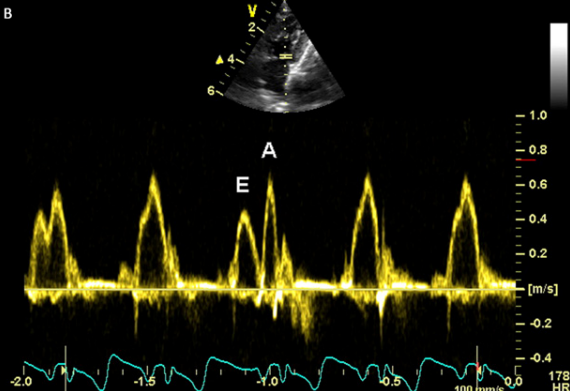

고양이 심장 초음파 검사를 할때면 대다수가 E,A peak가 합쳐져 버린다. 이때 약물을 통해 심박수를 낮출 수는 있지만 통상 약물에 대한 보호자의 거부때문에 약물 투여는 하지 못하는경우가 대부분이다.

안구압박법과 인중압박법을 제시하여 평가하고 있다.

| 방법 | 안구 압박 | 인중 |

| 자극 부위 | 닫힌 눈꺼풀 위의 안구 |

코 주변의 털이 없는 부분(비익) : 인중

|

| 자극 방식 | 부드럽게 누르기 | 부드럽게 마사지 |

| 효과 | 심박수 감소, 융합된 도플러 파형 분리 |

심박수 감소, 융합된 도플러 파형 분리

| 성공률 | 심박수 감소: 100%, 파형 분리: 71% |

심박수 감소: 100%, 파형 분리: 72%

| 지속 시간 | 짧음 (일반적으로 20초 미만) |

짧음 (일반적으로 15초 미만)

| 장점 | 빠르고 즉각적인 효과, 비침습적, 안전, 간편 |

빠르고 즉각적인 효과, 비침습적, 안전, 간편

| 단점 | 압박 강도 조절 필요, 개체 차이 존재, 효과 지속 시간 짧음 |

자극 강도 조절 필요, 개체 차이 존재, 효과 지속 시간 짧음

| 기타 | 양쪽 눈 압박이 더 효과적, 안와 주변 압박 중요 |

고양이 비익은 자극에 민감, 안구 압박과 병행 효과적